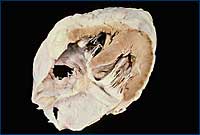

รูปหัวใจตัดตามยาว |

เป็นการตรวจหัวใจในระนาบตามยาวของหัวใจซึ่งจะเห็น หัวใจห้องขวา(right ventricle) หลอดเลือดใหญ่ (aorta) ลิ้นหัวใจหลอดเลือดแดงใหญ่ (aortic valve) หัวใจห้องบนซ้าย( left atrium)